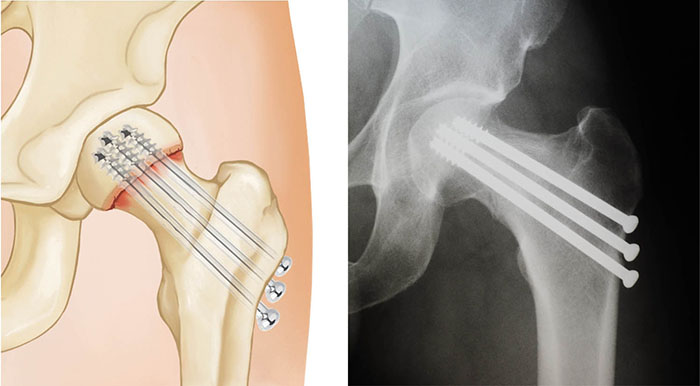

If a femoral neck fracture is not displaced (meaning the pieces of bone are properly aligned), the most common treatment is in-situ fixation.

In this procedure, surgical pins/screws or a plate and screw device are passed across the fracture site to hold the ball of the femur in place while the fracture heals. This procedure prevents the femoral head from dislodging or slipping off of the femoral neck, a situation that would require partial or total hip replacement. Both options provide stability to allow for immediate mobilization (getting out of bed and moving around)

femoral neck fracture

Nondisplaced femoral neck fracture

in-situ pending

In-situ pinning with three screws has been used to treat a nondisplaced femoral neck fracture.

X-ray courtesy of Stuart J. Fischer, MD, FAAOS

Fixation of Hip Fracture With Plate and Screw Device

X-ray showing treatment of a nondisplaced femoral neck fracture using a plate and screw device.